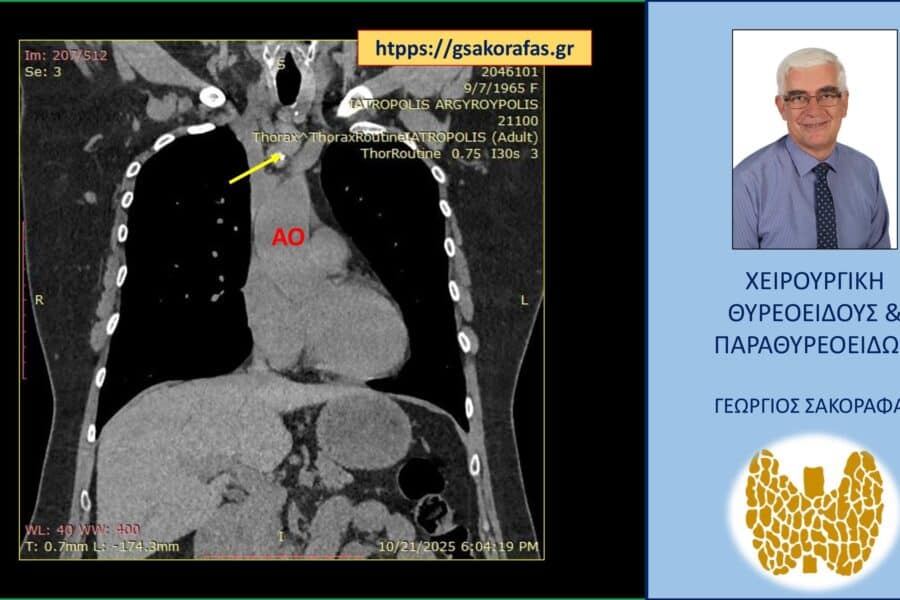

Θυρεοειδήςόζος θυρεοειδούς Έκτοπος θυρεοειδής (παθολογικός, ενδοθωρακικός όζος) σε ασθενή μας – εικόνες Έκτοπος θυρεοειδής (παθολογικός, ενδοθωρακικός όζος) σε ασθενή μας – εικόνες Παρουσίαση ασθενούς Αιτία…decade decade1 Μαΐου 2026